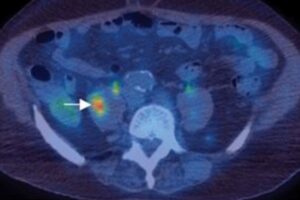

A PET/CT image highlighting a tumor. We talk about what cancer is, how it develops, and factors that contribute to it in this episode. https://every1dies.org